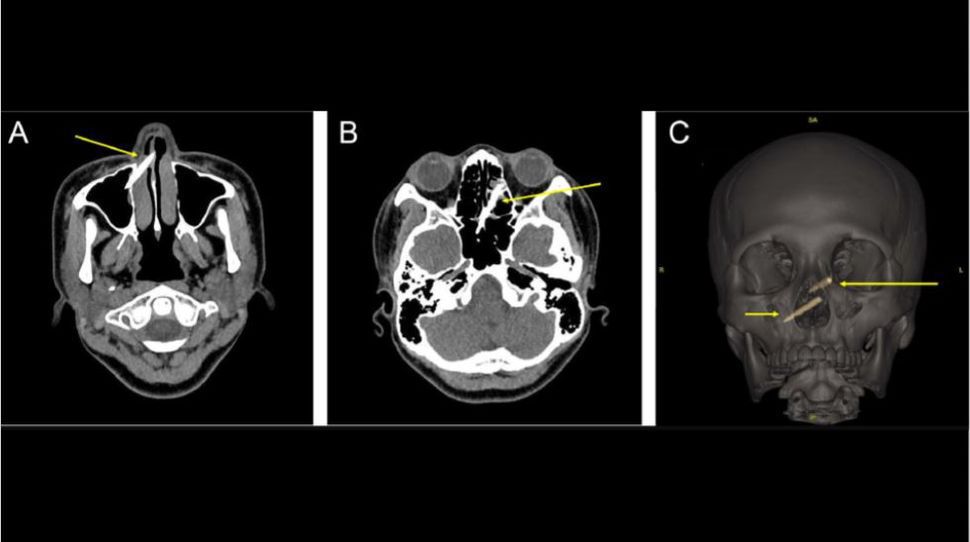

A woman in Taiwan had chopstick fragments embedded in her sinuses for a week without knowing it, after she had a violent fight with her sister. The 29-year-old woman went to the hospital after she was "attacked by her sister with plastic-wood chopsticks while at the dinner table," according to a report of the case, published June 24 in The Journal of Emergency Medicine. Doctors saw that she had two small cuts under her eye and on her nose, but an X-ray did not show anything unusual. However, one week later, the woman began to suspect that her injury was more serious than it appeared, Live Science previously reported. When she looked in the mirror, she thought she could see a gray object in her nose. Indeed, a second examination revealed pieces of chopstick that were penetrating her nasal septum, or the wall dividing the two nasal passages. A CT scan showed two chopstick pieces in her sinuses, with one embedded more deeply than the other. The woman needed surgery to remove the fragments, which were about 1.4 inches (3.5 cm) and 2 inches (5 cm) long, respectively, according to the report. She experienced no surgical complications.